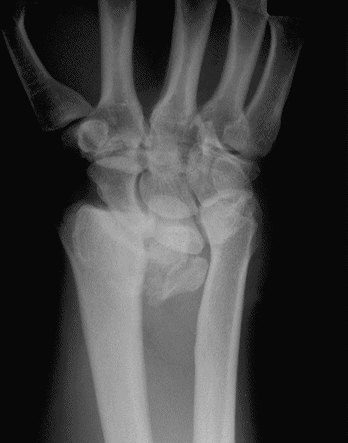

Case 2 Preop

Case 2 - closed reduction